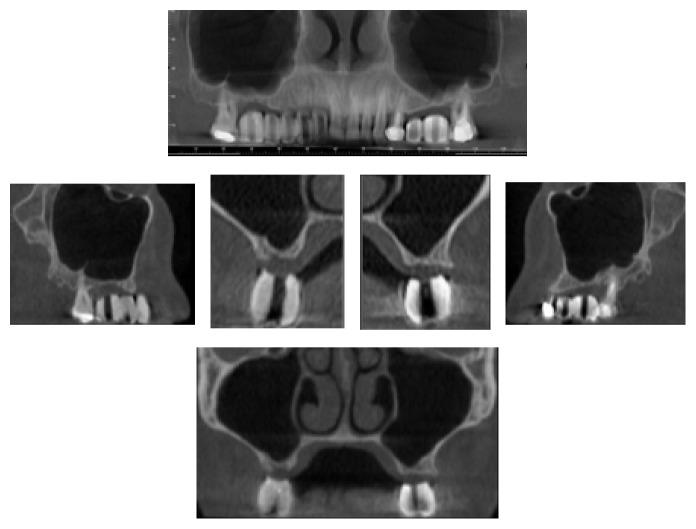

Aim. The aim of this study was to assess the success and the survival rate of dental implants placed in augmented bone after sinus lifting procedures. Material and Methods. 31 patients were mainly enrolled for a residual upper jaw crest thickness of 3 mm. CBCT scans were performed before and after the augmentation technique and at the follow-up appointments, at 3, 6, 12, 24, and up to 60 months. The follow-up examination included cumulative survival rate of implants, peri-implant marginal bone loss, and the height of sinus floor augmentation. Results. This retrospective study on 31 patients and 45 implants later inserted in a less than 3 mm crest showed excellent survival rates (99.5%), one implant was lost before loading due to an acute infection after 24 days, and two implants did not osteointegrate and were removed after 3 months. The radiological evaluation showed an average bone loss of 0.25 mm (±0.78 mm) at the first follow-up appointment (3 months) up to 0.30 mm (±1.28 mm) after 60-month follow-up. Conclusion. In this study it was reported how even in less than 3 mm thick crest a transcrestal technique can predictably be used with a long-term clinical and radiological outcome, giving patients excellent stability of the grafted material and healthy clinical results.

目的。本研究的目的是评估在鼻窦提升术后植入增骨部位的牙种植体的成功率和存活率。材料与方法。主要纳入了31例上颌嵴剩余厚度为3毫米的患者。在增骨技术前后以及随访时进行CBCT扫描,随访时间为3、6、12、24个月直至60个月。随访检查包括种植体的累积存活率、种植体周围边缘骨丢失以及鼻窦底提升的高度。结果。这项对31例患者和后来植入不足3毫米嵴中的45颗种植体的回顾性研究显示出优异的存活率(99.5%),一颗种植体在加载前因24天后的急性感染而丢失,两颗种植体未骨整合并在3个月后被取出。放射学评估显示,在首次随访(3个月)时平均骨丢失为0.25毫米(±0.78毫米),至60个月随访后为0.30毫米(±1.28毫米)。结论。在本研究中报告了,即使在上颌嵴厚度不足3毫米的情况下,穿嵴技术仍可预测地用于获得长期临床和放射学结果,为患者提供移植材料的优异稳定性和健康的临床结果。